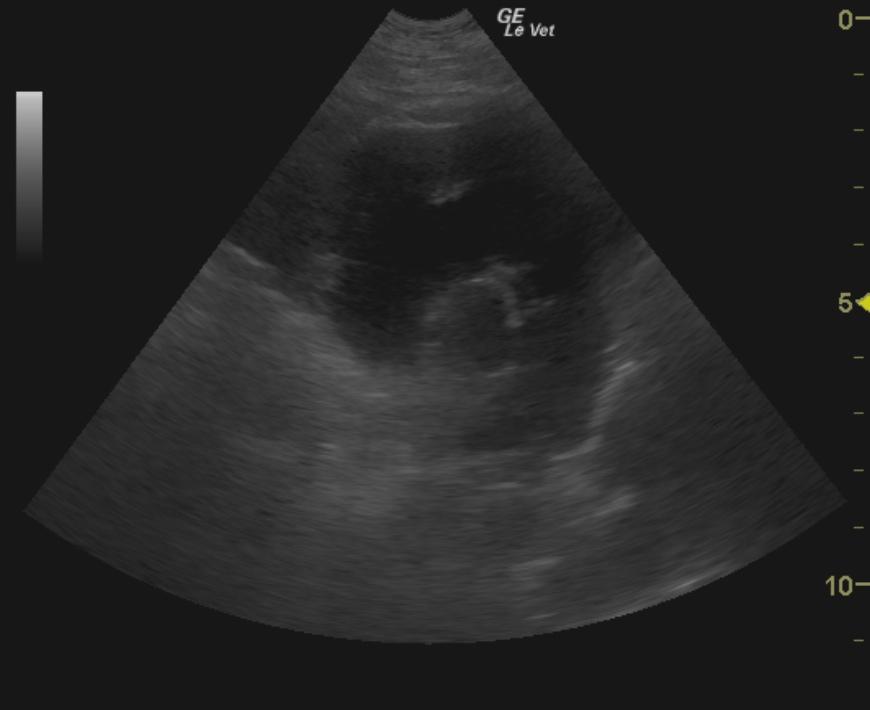

A 10-year-old neutered male Boston Terrier dog was presented for possible seizure activity. A grade II/VI heart murmur and left submandibular lymphadenomegaly were present on physical examination. Abnormalities on CBC and blood chemistry included neutrophilia, eosinopenia, thrombocytosis, elevated ALP activity, and elevated CK. T4 was within normal limits. The patient was treated with enalapril and clindamycin pending ultrasound.